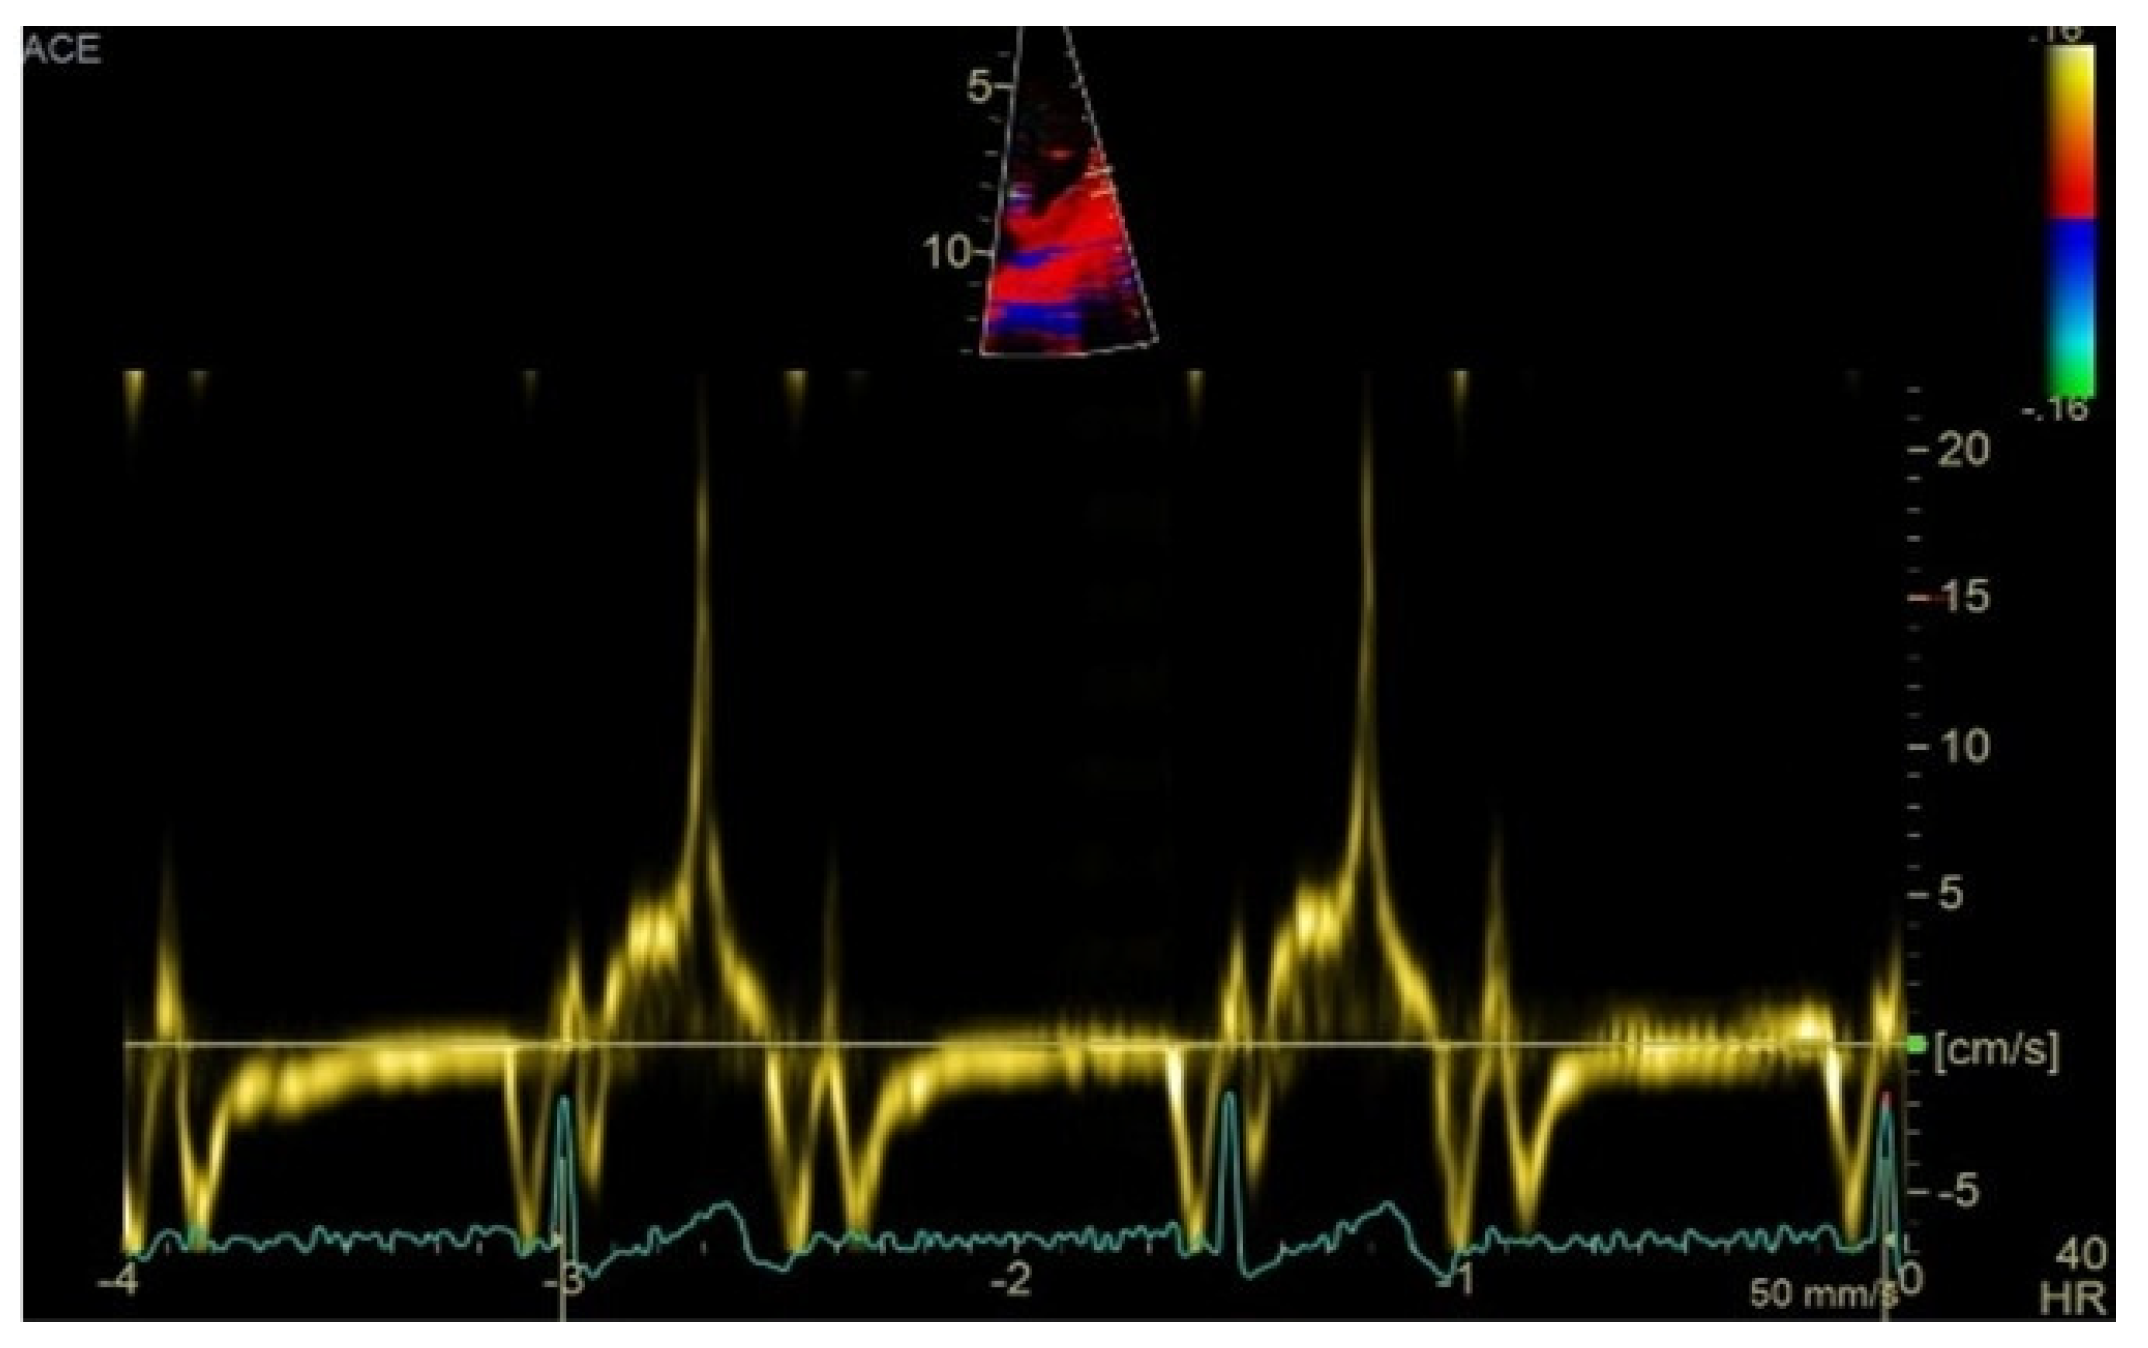

Figure 3.

High-velocity spike (21 cm/s) between mid-systole to late-systole using tissue Doppler imaging on the lateral mitral annulus. Known as the Pickelhaube sign, this sharp annular spike resembles the spike that adorns the Pickelhaube helmet, historically worn by the German military. It has been proposed as a marker of arrhythmogenic mitral valve prolapse.

Comprehensive echocardiographic assessment is crucial [4,61] and should include evaluation of mitral valve morphology and mitral annular diameter [62]. Mitral annular dilatation and flattening are frequently associated with mitral annular disjunction, which should be evaluated in terms of presence and length. A distinct echocardiographic feature—termed the “Pickelhaube sign”—described by Muthukumar et al. [63], represents a sharp mid-to-late systolic velocity spike at the lateral mitral annulus seen on tissue Doppler imaging, and has been proposed as a marker of arrhythmogenic mitral valve prolapse.